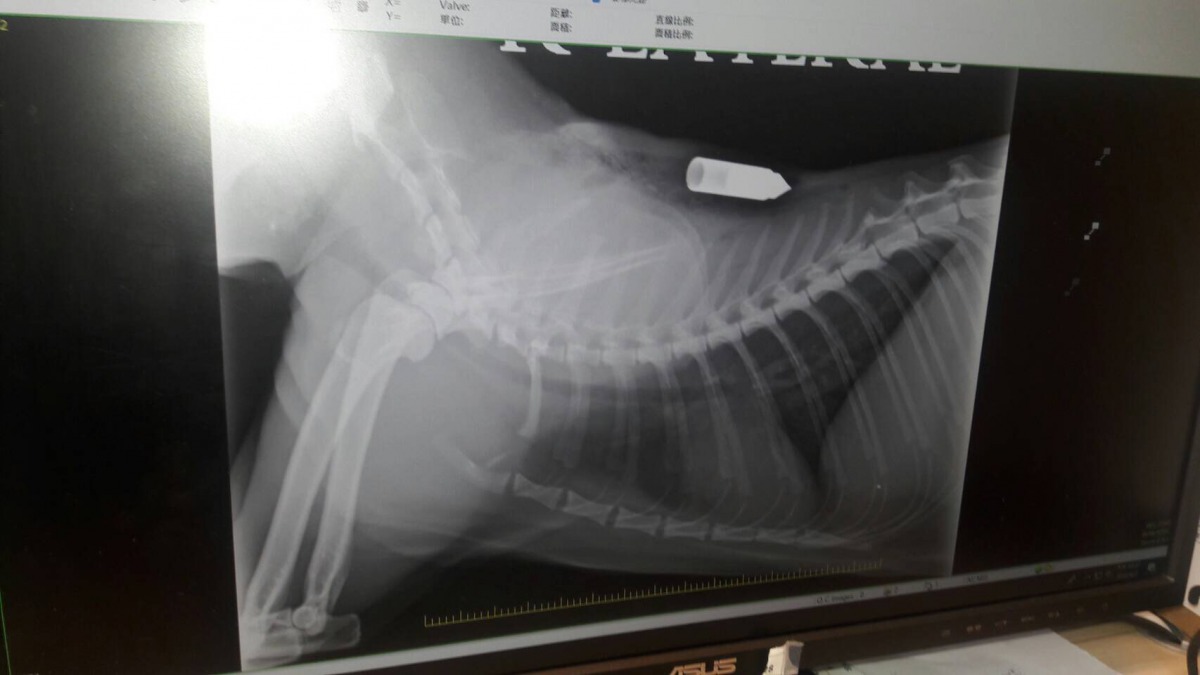

李姓飼主表示,8月2日上午9點突然間就聽見客廳傳來貓咪的哀號聲,趕到客廳一看發現竟然是飼養的貓咪左上肩插著一支生鏽的箭,當下趕緊將「橘子」送醫急救,經過獸醫師檢查,所幸箭沒有射中要害,手術後順利將箭取出並包紮之後就把「橘子」帶回家休養。